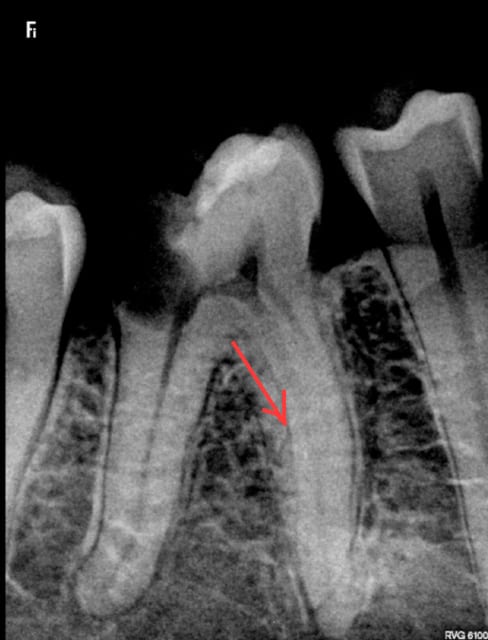

Que dalle dent vivante.

Radio cone en place , cone scellé, cone condensé. Pas de bip intempestif au localisateur d'apex, je vois pas ou j'ai fait une connerie. Pour une fois ou je mets pas la digue ( urgence) . -)

Sur la radio pré op ( avant anesthésie) on dirait qu'il y a un petit quelque chose sur la racine mésiale.

On dirait que l'image commençait déjà à apparaître sur la radio cone + pate non foulée.

La légère radio opacité de cette image curieuse ne m'inquiète pas du tout.

Je visualise, peut être à tort, autour de la racine mésiale une pseudo image radioclaire.....

percer une racine ca me semble difficile quand même. Mais c'est vrai que l'image ne m'évoque qu'une fuite de pâte dans le trajet de l'aiguille. serais tu juste tangent et a cote d'un canal secondaire?